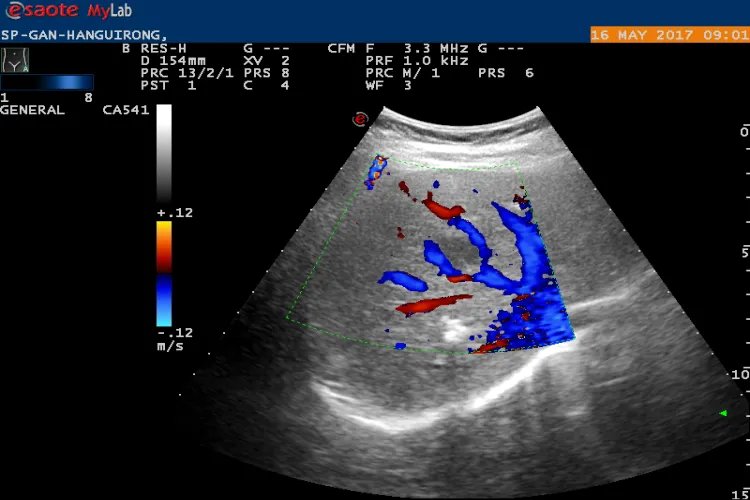

的有关信息介绍如下:彩超是彩色多普勒超声的简称,可对血管、腹腔脏器、心脏、子宫及附件、小器官、前列腺及精囊等全身性脏器进行检查。